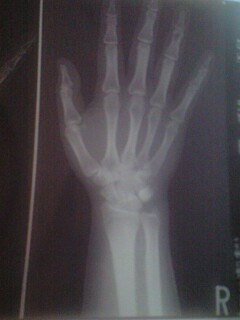

右手関節の状態がかなり悪化したので

近所にある大きな病院を受診する事に。

まずこの痛みを取って下さい。。

お願いっ三上先生!!

初診の時に持って行く為に預かった

自分の右手のレントゲン写真。。

骨はキレイ。

異常所見ナシ。

しいて云うならがっしりしすぎ?

骨格マニアなのでうはうは観賞(笑